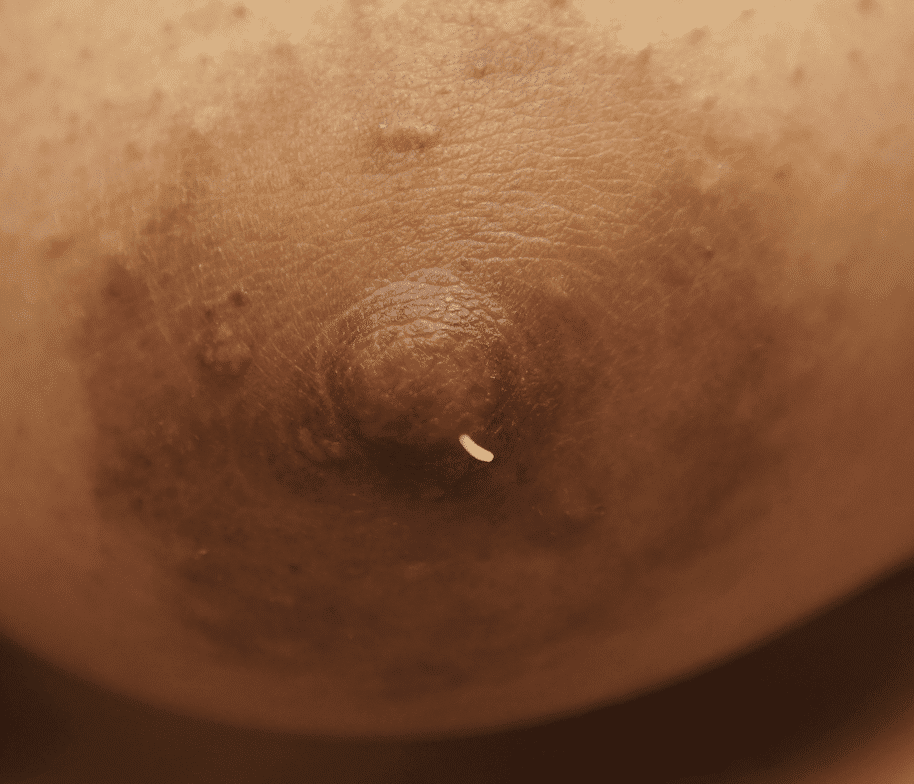

Sebum emanating from nipple sebaceous cyst.